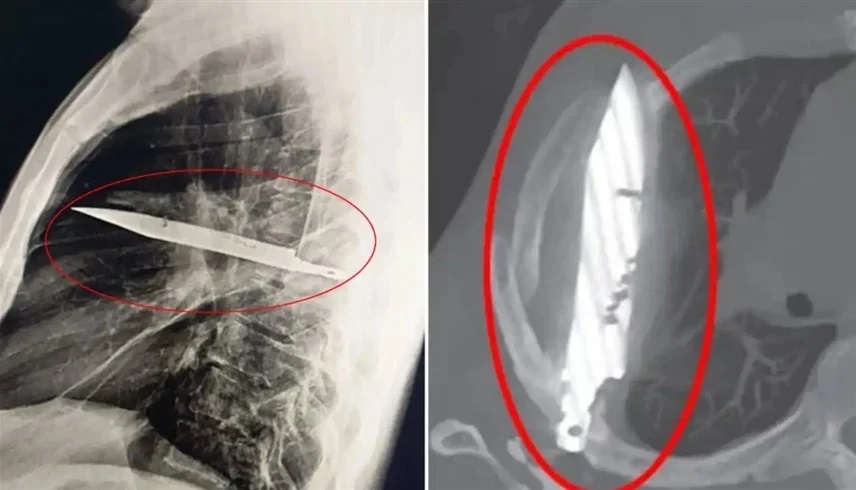

وأظهرت الفحوص بالأشعة وجود جسم معدني ضخم اخترق جسده عبر لوح الكتف الأيمن واستقر على مسافة خطيرة من أعضائه الحيوية، من دون أن يلحظ الأمر طوال هذه السنوات. وذكر المريض أنه أصيب في وجهه وظهره وصدره وبطنه خلال مشاجرة عنيفة قبل نحو عقد، وتلقى علاجاً حينها، لكنه لم يكن يعلم أن السكين بقي عالقاً داخل جسده.

وأجرى الجراحون عملية دقيقة لاستخراج السكين وتصريف الصديد الناتج عن تلف الأنسجة، وقضى المريض 24 ساعة في العناية المركزة ثم 10 أيام في الجناح العام قبل أن يتعافى ويغادر المستشفى. ووصفت Journal of Surgical Case Reports الحالة بأنها من أندر الوقائع التي ينجو فيها مريض رغم بقاء جسم غريب بهذا الحجم داخل جسده لسنوات.